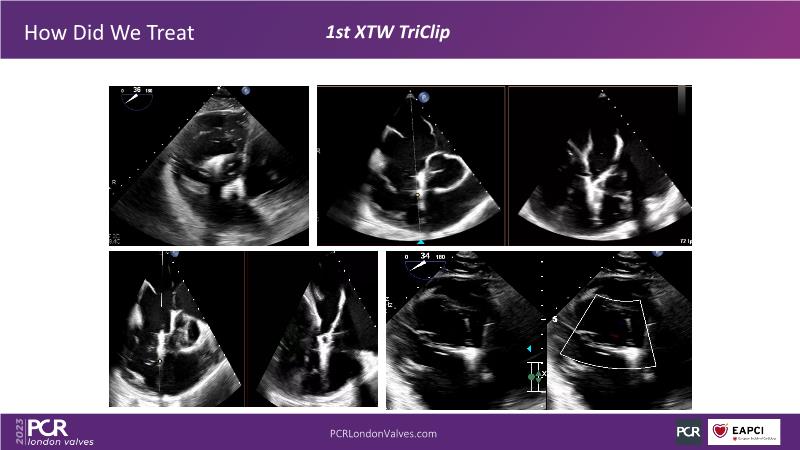

This session offers an opportunity to engage in a real case discussion led by an advanced Heart Team. Participate in discussions on controversial decision-making scenarios and stay informed about the latest clinical evidence related to MitraClip, Tendyne, and TriClip therapies.